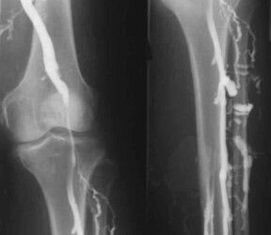

Die gebräuchlichste instrumentelle Diagnosemethode ist die Ultraschalluntersuchung der venösen Gefäße der Beine. Mit dieser Technik können Sie das Gefäßsystem visualisieren und den Fortschritt des pathologischen Prozesses erkennen.

- Phlebographie.